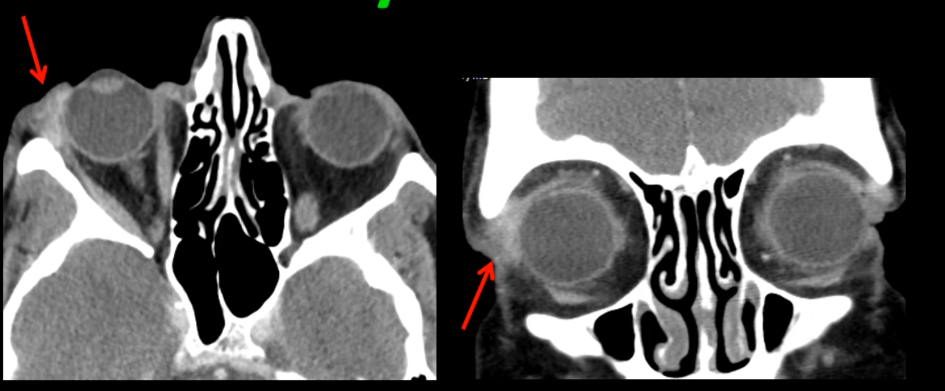

CT

- Tuméfaction ovoide près du canthus interne

- Souvent cellulite préseptale associée